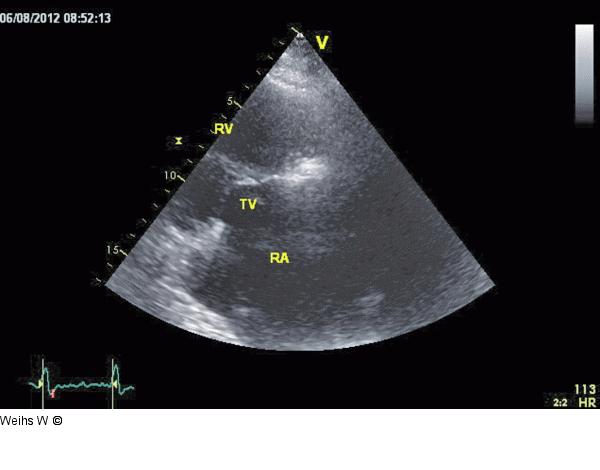

Abbildung 2: Rechtsventrikulärer Einflusstrakt Parasternale Darstellung des rechtsventrikulären Einflusstraktes mit dem rechten Vorhof (RA), dem rechten Ventrikel (RV) und der Trikuspidalklappe (TV). In diesem Schnitt kann das posteriore Trikuspidalsegel eingesehen werden. |

Parasternale Darstellung des rechtsventrikulären Einflusstraktes mit dem rechten Vorhof (RA), dem rechten Ventrikel (RV) und der Trikuspidalklappe (TV). In diesem Schnitt kann das posteriore Trikuspidalsegel eingesehen werden. |